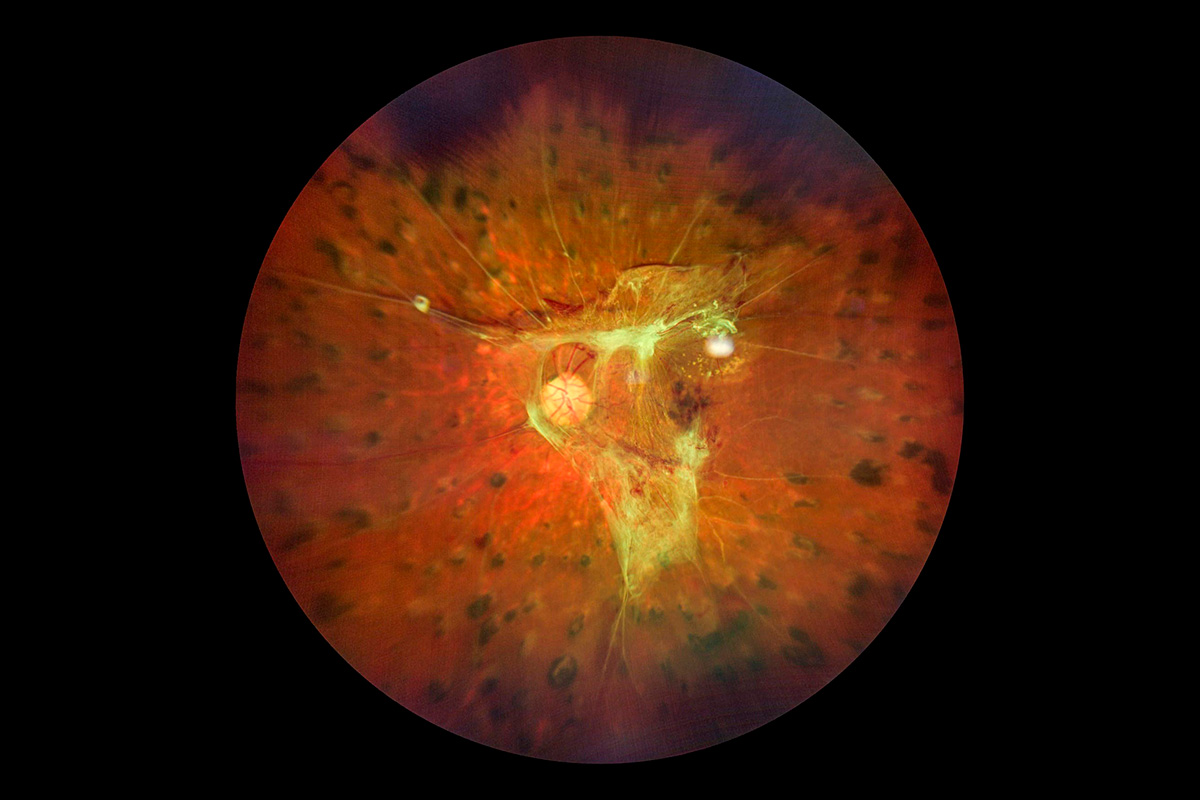

Edema de papila: es la inflamación de la cabeza del nervio óptico (parte visible del nervio en la retina), puede ser causado por inflamación, isquemia, traumatismo, infección del nervio óptico o aumento de la presión interior del cerebro a consecuencia de tumores, meningitis o encefalitis.

- Angiografía con fluoresceína y fotografía de fondo de ojo: a través del servicio de imagenología se obtienen fotografías de fondo de ojo para observar el nervio óptico, la retina y la mácula. El procedimiento se realiza de lunes a viernes de 8:00 a 15:00 horas, consiste en dilatar la pupila para obtener imágenes con equipo especializado